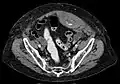

A rectus sheath hematoma is an accumulation of blood in the sheath of the rectus abdominis muscle. It causes abdominal pain with or without a mass.

The hematoma may be caused by either rupture of the epigastric artery or by a muscular tear. Several factors have been identified as predisposing risks for rectus sheath hematoma, including coughing, straining, exercise, hypertension, obesity, previous abdominal surgery, subcutaneous injection, trauma and anticoagulant therapy. With an ageing population and the widespread use of anticoagulant medications, there is evidence that this historically benign condition is becoming more common and more serious.[1] Anticoagulant therapy is used to treat many diseases. However, in the COVID-19 pandemic, anticoagulant therapy was frequently used and therefore the incidence of rectus sheat hematoma increased. [2][3] Given that thrombotic events have been documented in numerous studies, it is advisable to initiate prophylactic and anticoagulant treatment during the early phase of COVID-19 disease. [4]